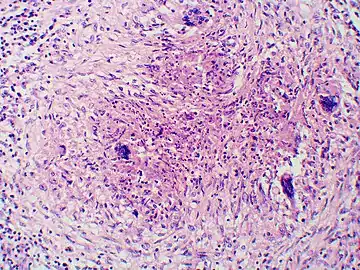

In disseminated blastomycosis, the large Blastomyces yeast cells translocate from the lungs and are trapped in capillary beds elsewhere in the body, where they cause lesions. The skin is the most common organ affected, being the site of lesions in approximately 60% of cases.[20] The signature image of blastomycosis in textbooks is the indolent, verrucous or ulcerated dermal lesion seen in disseminated disease. Osteomyelitis is also common (12–60% of cases). Other recurring sites of dissemination are the genitourinary tract (kidney, prostate, epididymis; collectively ca. 25% of cases) and the brain (3–10% of cases).[20] 40% of immunocompromised individuals have CNS involvement and present as brain abscess, epidural abscess or meningitis.

Once suspected, the diagnosis of blastomycosis can usually be confirmed by demonstration of the characteristic broad based budding organisms in sputum or tissues by KOH prep, cytology, or histology.[27] Tissue biopsy of skin or other organs may be required in order to diagnose extra-pulmonary disease. Blastomycosis is histologically associated with granulomatous nodules.